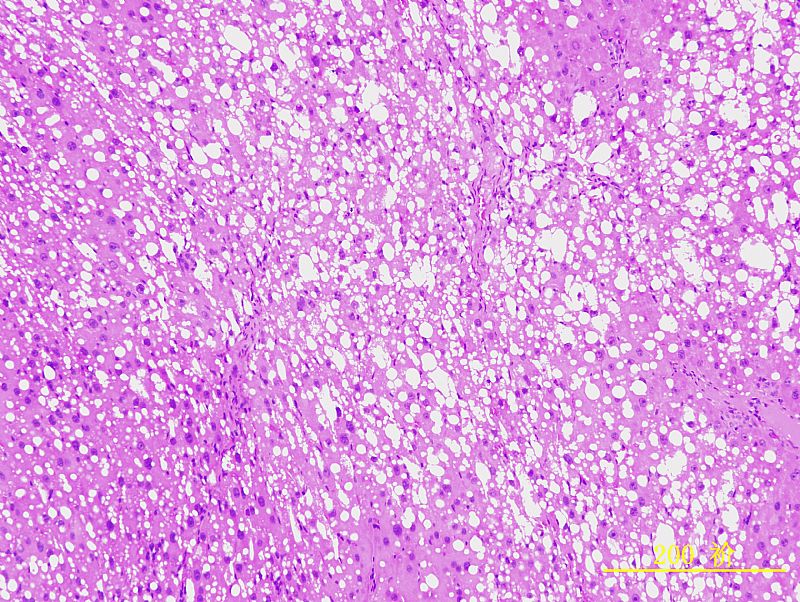

请教各位虫子,我做的是肝纤维模型,皮下注射CCl4 8周造模。每周两次,3ml/kg,40%CCl4。 因为对肝组织的组织形态没有深入的学习,对肝组织的具体病变描述无从入手,不知肝细胞脂肪病变、炎性浸润等是怎样的,附上几张实验图片(HE&Sirus red),请教各位行家,还望各位老师不吝赐教,一一指点下!谢谢大家,另外祝大家节日快乐呵呵 |